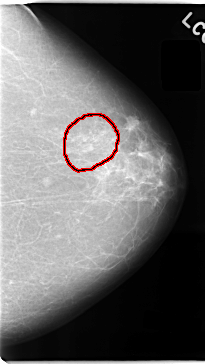

C_0040_1.LEFT_MLO

LEFT_MLO LINES 5944 PIXELS_PER_LINE 3096 BITS_PER_PIXEL 12 RESOLUTION 50 OVERLAY

FILE: C_0040_1.LEFT_MLO.OVERLAY

TOTAL_ABNORMALITIES 1

ABNORMALITY 1

LESION_TYPE MASS SHAPE LOBULATED MARGINS OBSCURED

ASSESSMENT 3

SUBTLETY 3

PATHOLOGY MALIGNANT

TOTAL_OUTLINES 1

BOUNDARY